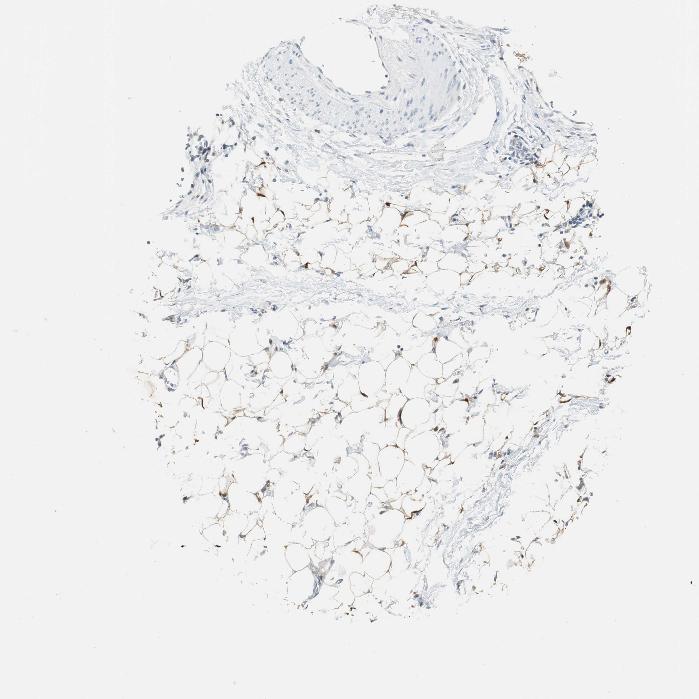

SOFT TISSUE 1 - Antibody stainingi

Antibody staining in the annotated cell types in the current human tissue is reported as not detected, low, medium, or high, based on conventional immunohistochemistry profiling in selected tissues. This score is based on the combination of the staining intensity and fraction of stained cells.

Each image is clickable and will lead to virtual microscopy that enables deeper exploration of all samples and also displays staining intensity scores, fraction scores and subcellular localization as well as patient and tissue information for each sample.

Antibody HPA006493

Fibroblasts Not detected

Peripheral nerve Not detected